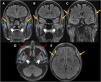

Whole-body magnetic resonance imaging (MRI, Fig. 2) revealed diffuse muscle edema consistent with active DM. Brain MRI (Fig. 3) ruled out central causes and demonstrated an unusual finding of bilateral edema of the masticatory muscles.

Diagnosis and developmentWhole-body MRI revealed diffuse muscle edema consistent with active DM and an unusual finding of bilateral masticatory muscle edema, correlating with chewing and swallowing difficulties. Brain MRI ruled out central causes, confirming that masticatory muscle involvement was the likely cause of symptoms. Despite immunosuppressive therapy, the patient required nasogastric nutritional support.

DiscussionDM primarily affects proximal limb muscles, and MRI findings such as diffuse edema and the “honeycomb” pattern are associated with severe disease, especially in paraneoplastic cases.1,2 However, masticatory muscle edema has not been previously described.3 One hypothesis suggests a selective autoimmune phenomenon affecting highly active muscle groups, while another considers an atypical inflammatory infiltration in paraneoplastic DM.4 The correlation with dysphagia suggests MRI could aid in evaluating refractory symptoms.5 Recognizing this atypical manifestation may influence therapeutic decisions and highlights the importance of detailed imaging in persistent cases. Further studies are needed to determine the prevalence and clinical significance of masticatory muscle involvement in DM. This case expands the spectrum of DM-related muscle involvement and reinforces the role of MRI in detecting atypical patterns (Figs. 1–3).

Brain MRI in fluid-attenuated inversion recovery (FLAIR sequence) – coronal (A–C) and axial (D, E) images. Notable bilateral and symmetrical edema of the masticatory muscles, involving the superficial temporalis (orange arrows), masseters (blue asterisks), and pterygoids (white head arrows). Cosmetic filling material was present in the anterolateral facial subcutaneous (red dashed arrows).